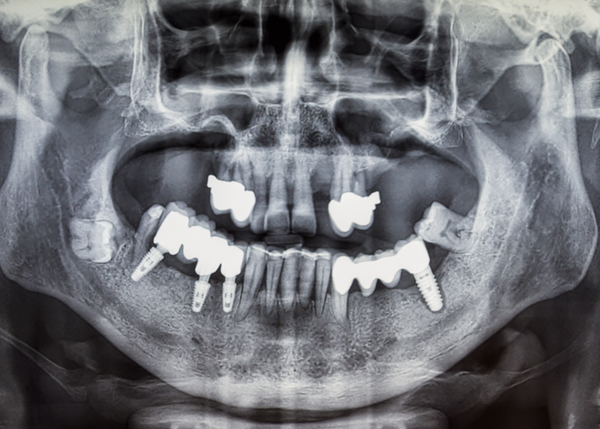

- 40대 남성, 치료 후 3개월

- 상·하악 풀마우스 임플란트

- 40대 남성, 치료 후 3개월

- 상·하악 풀마우스 임플란트